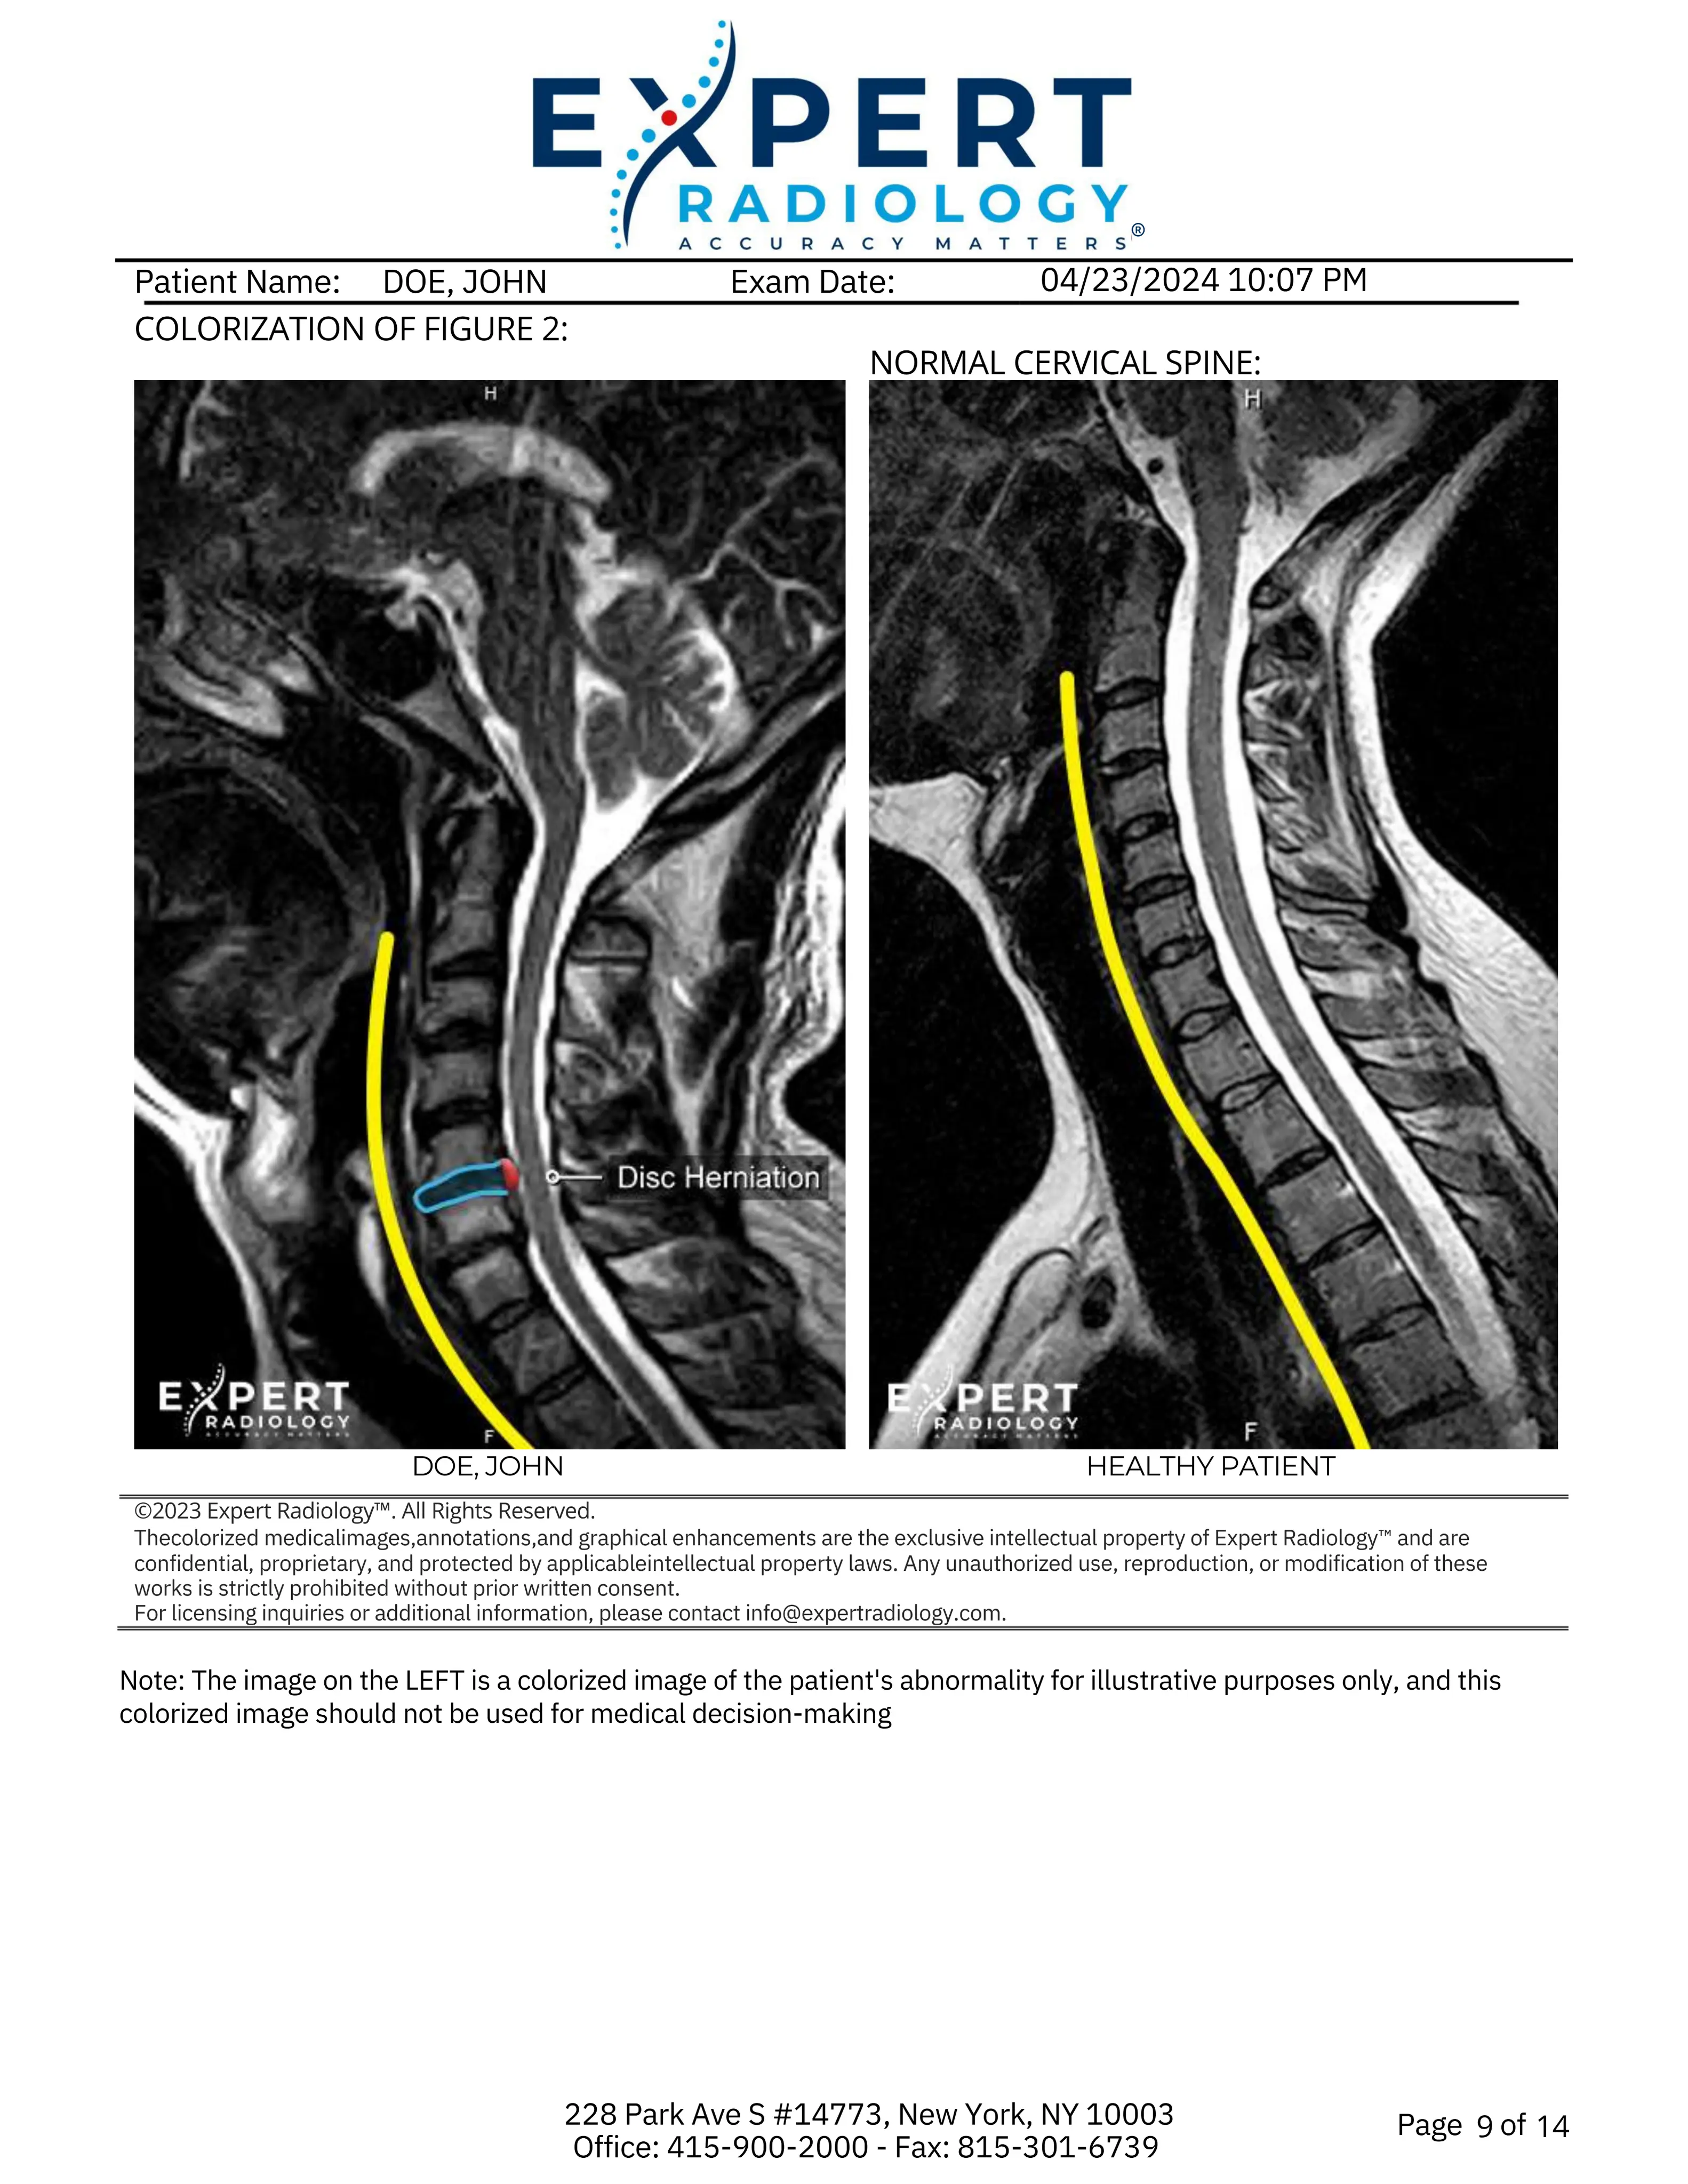

Key images highlighting the abnormalities, with concise descriptions and color-coded visuals that clearly identify pathology for ordering physicians, patients, and their representatives.

Custom illustrations showing the pathology. Useful for patients, physicians, and advocates involved in the patient's recovery.